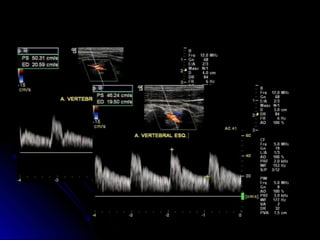

VertebralVertebral

Espectral com VPS e VDEspectral com VPS e VD

Documentar a correção do ângulo DopplerDocumentar a correção do ângulo Doppler

Art vertebral estenose e insuf

aórtica

Figure 6. Bisferious vertebral artery Doppler waveform in a

patient with severe aortic stenosis and mild aortic incompetence.

Br J Radiol. 2004 Jan;77(913):15-20.